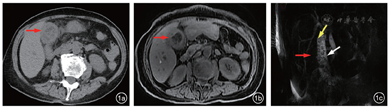

患者女性,72岁,因“突发右上腹疼痛7 d”于2020年1月28日急诊入院。入院前7 d突发右上腹疼痛,渐出现皮肤巩膜黄染、小便浓茶色,后出现寒战、发热,体温最高达39 ℃,无咳嗽、咳痰,就诊于我院发热门诊,胸部CT报告双肺支气管炎、下叶肺炎、双侧胸腔积液,结合无疫区、疫情接触史,初步排除新型冠状病毒肺炎(coronavirus disease 2019,COVID-19)后,转急诊外科,腹部CT显示胆囊结石、胆囊炎,经医院COVID-19疫情专家组批准,以“急性结石性胆囊炎”收住院,安排普外科单间隔离病房。入院查体:全身皮肤巩膜重度黄染,右上腹压痛,Murphy氏征阳性,肝区叩痛。入院后辅助检查:血常规白细胞10.6×109/L,中性粒细胞比例88.7%,血红蛋白70 g/L,血高敏C反应蛋白111.12 mg/L,肝功能总胆红素565.57 μmol/L,直接胆红素289.90 μmol/L,丙氨酸氨基转移酶79 U/L,血清糖类抗原19-9(CA19-9)8454 U/ml,腹部CT报告胆囊结石、胆囊炎、肝内胆管和胆总管扩张,磁共振胰胆管成像报告胆囊结石、胆囊炎、胆总管下段结石(图1)。初步诊断:急性梗阻性化脓性胆管炎、急性结石性胆囊炎,胆道恶性肿瘤待排。

该患者术前高热(体温最高达39 ℃)、严重黄疸(总胆红素高达565.57 μmol/L)、CA19-9很高(8454 U/mL)、胸部CT(双肺支气管炎、下叶肺炎、双侧胸腔积液),既要与COVID-19严格鉴别,又要明确胆总管梗阻原因。患者入院后的MRCP检查,在胆道良恶性梗阻鉴别上起到了关键作用。